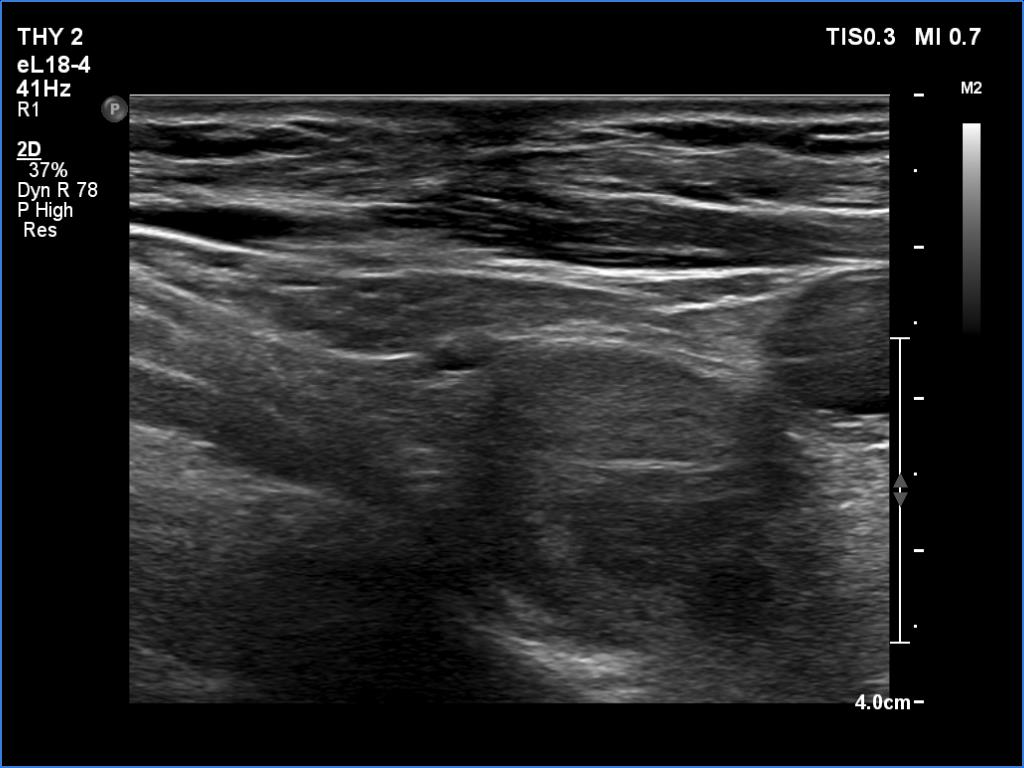

Follow-up investigation 6 months after first visit (ultrasonographic picture 4)

Lower to the right lobe, longitudinal view. The large hypoechoic mass is located dorsal and upper to the carotid artery.